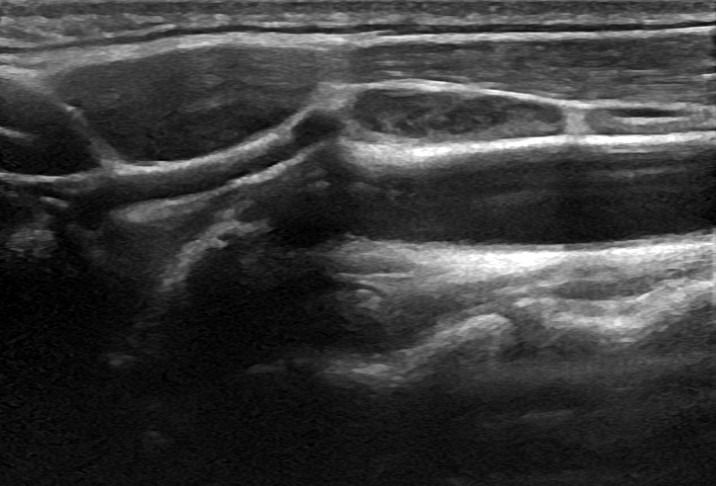

Το Υπερηχογράφημα Λεμφαδένων Τραχήλου προσφέρει μια εμπεριστατωμένη εικόνα των λεμφαδένων, με χρήση της προηγμένης τεχνολογίας των ειδικών κεφαλών υψηλής συχνότητας, Έγχρωμου Doppler, Power Doppler και B-Flow, καθώς και της Ελαστογραφίας. Με αυτές τις τεχνικές είναι δυνατή η γρήγορη και αξιόπιστη αξιολόγηση της μορφολογίας των λεμφαδένων και η αναγνώριση των χαρακτηριστικών τους με μεγάλη ακρίβεια.

Η Ελαστογραφία αποτελεί ένα εξαιρετικά χρήσιμο εργαλείο στο Υπερηχογράφημα Λεμφαδένων Τραχήλου. Με την Ελαστογραφία, μπορούμε να αξιολογήσουμε την ελαστικότητα των λεμφαδένων, βοηθώντας έτσι στη διάκριση μεταξύ καλοήθων και διηθημένων λεμφαδένων. Αυτό είναι ιδιαίτερα σημαντικό στη διαδικασία της διάγνωσης.